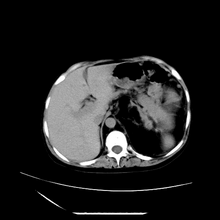

女性,41岁,发现左腹部包块3年,现行ct检查,检查前做过静脉肾盂造影。

左侧低密度区是脂肪密度,中间可见条索状软组织样密度影,现主要想知道左肾前下缘圆形软组织样密度影,内见低密度水样密度影,这是什么?

脾脏增大,左肾后方脂肪增多,脊柱前方脂肪增多,左肾窦脂肪增多,左肾变形,双肾积水以左侧为著,左肾内侧及上方见环形软组织肿物影,内部低密度区,考虑1盆腹腔/腹膜后及左肾窦脂肪增多症2左肾内侧病灶可能为左肾上腺病灶,可能为脂肪增多的原凶

1)考虑左肾替代性脂肪瘤病;不排除左肾错构瘤。2)双肾积水。

肾窦脂肪瘤病及肾替代性脂肪瘤病被认为是脂肪增殖程度不同的一种疾病。正常情况下肾窦内有少量脂肪组织充填,在某种情况下肾实质会发生萎缩,而以肾窦、肾门为中心脂肪或(和)纤维组织可出现增殖,当增殖局限在肾窦、肾门区时称为肾窦脂肪瘤,若同时部分或全部取代了萎缩破坏的肾实质时称为肾替代性脂肪瘤病。

ct典型表现为以肾窦肾门为中心大量弥漫性脂肪积聚,鹿角状结石及萎缩的肾实质。合并肾周感染时,肾轮廓不清,周围有粘连性改变。

诊断rsl的必备条件是肾窦、肾门的脂肪组织增生和肾实质的萎缩,而且本例因为ivp后扫描不好判断有无肾结石但可能性较小;另外,占位效应显著,脾后缘都受压了,肾门以下肾实质残缺,支持肾脏错构瘤.

左肾周脂肪堆积征【原因?】,双肾逆行造影术后;脾大【原因?】